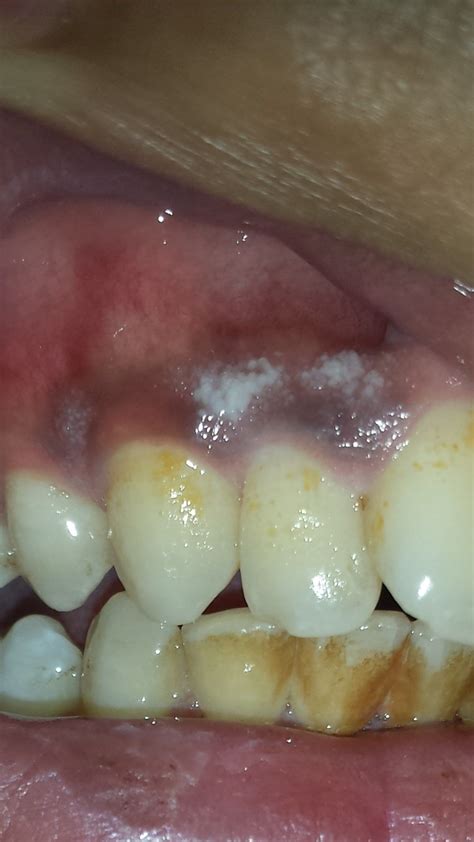

When you notice gums bleeding randomly, it is rarely a coincidence. The primary cause is almost always an accumulation of dental plaque—a sticky film of bacteria that forms on the teeth. If this plaque is not removed through consistent brushing and flossing, it irritates the gum tissue, leading to inflammation known as gingivitis. When the tissue is inflamed, it becomes fragile and prone to bleeding even with minimal pressure.

Distinguishing Gingivitis from Periodontitis

It is crucial to understand the progression of gum disease. Gingivitis is the early, reversible stage characterized by red, swollen, and bleeding gums. If left unaddressed, it can advance to periodontitis. In this stage, the infection spreads below the gum line, damaging the bone and supporting structures of your teeth. Once periodontitis sets in, the damage is often irreversible, and professional intervention is mandatory to prevent tooth loss.

⚠️ Note: If your gums bleed randomly and you also experience loose teeth, persistent bad breath, or receding gum lines, consult a dental professional immediately, as these are advanced indicators of periodontal disease.